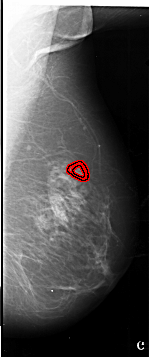

A_1012_1.LEFT_MLO

RIGHT_MLO LINES 6781 PIXELS_PER_LINE 2821 BITS_PER_PIXEL 16 RESOLUTION 42 OVERLAY

FILE: A_1012_1.RIGHT_MLO.OVERLAY

TOTAL_ABNORMALITIES 1

ABNORMALITY 1

LESION_TYPE MASS SHAPE IRREGULAR MARGINS SPICULATED

ASSESSMENT 4

SUBTLETY 2

PATHOLOGY MALIGNANT

TOTAL_OUTLINES 2

BOUNDARY

CORE